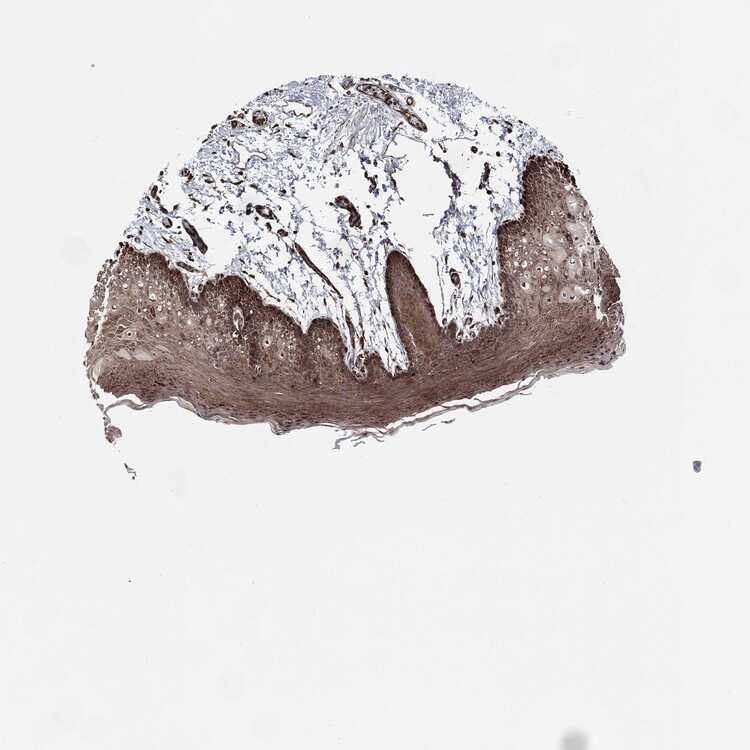

TISSUE PRIMARY DATA ORAL MUCOSA Show tissue menu

ORAL MUCOSA - Antibody stainingi

Antibody staining in the annotated cell types in the current human tissue is reported as not detected, low, medium, or high, based on conventional immunohistochemistry profiling in selected tissues. This score is based on the combination of the staining intensity and fraction of stained cells.

Each image is clickable and will lead to virtual microscopy that enables deeper exploration of all samples and also displays staining intensity scores, fraction scores and subcellular localization as well as patient and tissue information for each sample.

Antibody HPA019060Antibody HPA048820

Squamous epithelial cells LowMedium